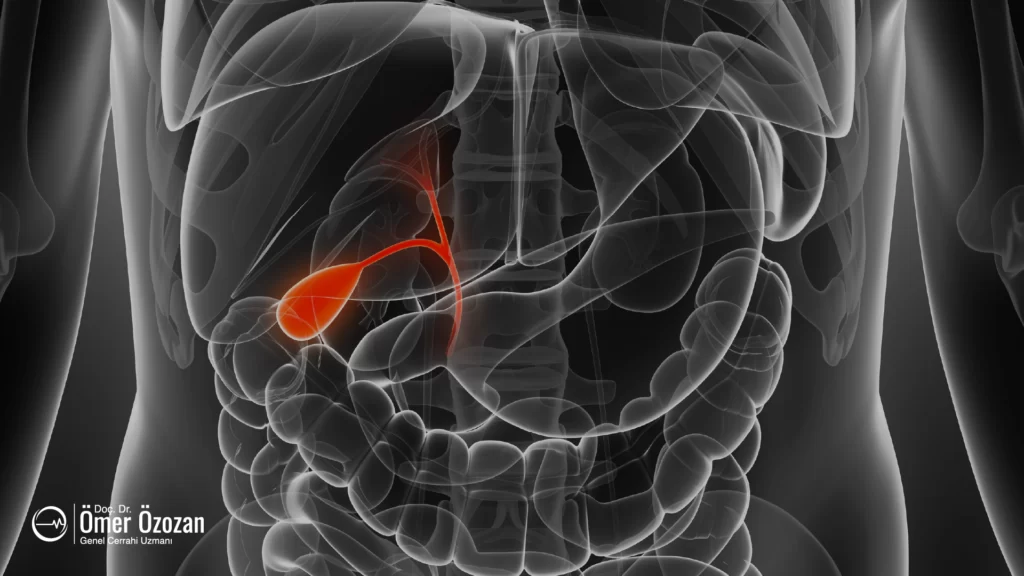

Safra Kesesi ve Fonksiyonları

Safra kesesi, karaciğerin hemen altında yer alan küçük, armut şeklinde bir organdır. Yaklaşık 7-10 cm uzunluğunda ve 3-4 cm genişliğinde olan bu organ, karaciğer tarafından üretilen safranın depolandığı ve konsantre edildiği yerdir. Safra kesesinin iç yüzeyi mukozal tabakayla kaplıdır ve bu tabaka, safrayı yoğunlaştırma görevini üstlenir. Ayrıca, safra kesesi duvarında düz kas lifleri bulunur. Bu kaslar, sindirim sırasında kasılarak safra sıvısının ince bağırsağa salınmasını sağlar. Safra kesesinin alt kısmı, kistik kanal aracılığıyla ana safra kanalıyla bağlantılıdır. Bu kanal, safranın karaciğerden safra kesesine ve safra kesesinden ince bağırsağa taşınmasını sağlar.

Safra Üretimi ve Depolanması

Safra, karaciğer hücreleri tarafından sürekli olarak üretilen sarı-yeşil renkli bir sıvıdır. Bu sıvı, karaciğerin hepatosit adı verilen hücrelerinde üretilir ve ince kanalcıklar (kanaliküller) aracılığıyla safra yollarına geçer. Safra yolları, kistik kanal aracılığıyla safra kesesine bağlanır ve safra burada depolanır. Safra kesesi, safra sıvısını depolamakla kalmaz, aynı zamanda onu yoğunlaştırır. Konsantrasyon işlemi sırasında, safra kesesi suyun bir kısmını emer ve böylece safra daha yoğun bir hale gelir. Bu yoğunlaşmış safra, sindirim sırasında daha etkili bir şekilde kullanılmak üzere depolanır.

Safra Kesesinin Sindirimdeki Rolü

Safra kesesi, sindirim sürecinde önemli bir rol oynar. Yağlı bir yemek yediğimizde, mide tarafından sindirim başlatılır ve bu süreç ince bağırsağa sinyal gönderir. İnce bağırsakta bulunan hormonlar, safra kesesinin kasılmasını ve safra sıvısının duodenuma (on iki parmak bağırsağı) salınmasını sağlar. Salınan safra, ince bağırsakta yağların emilimi ve sindirimi için gereklidir. Safra, yağları daha küçük damlacıklara ayırarak, enzimlerin bu yağlara erişimini kolaylaştırır ve yağların sindirimini hızlandırır. Ayrıca, safra asitleri, yağların emilimini artırarak vücutta kullanılmasını sağlar. Safra aynı zamanda yağda çözünen vitaminlerin (A, D, E, K) emilimine de yardımcı olur.

Safra kesesinin düzgün çalışması, sindirim sürecinin etkinliği için kritik öneme sahiptir. Safra kesesinde taşlar veya polipler gibi sorunlar oluştuğunda, bu durum safra akışını engelleyebilir ve sindirim sürecinde aksamalara yol açabilir. Örneğin, safra taşları safra kanalını tıkayabilir ve safra kesesinin iltihaplanmasına (kolesistit) neden olabilir. Bu tür durumlar, genellikle safra kesesinin cerrahi olarak çıkarılmasını gerektirebilir. Ancak, safra kesesi olmadan da yaşam mümkündür; bu durumda safra, doğrudan karaciğerden ince bağırsağa akıtılır, ancak bu süreç daha az kontrollüdür ve sindirim sorunlarına yol açabilir.